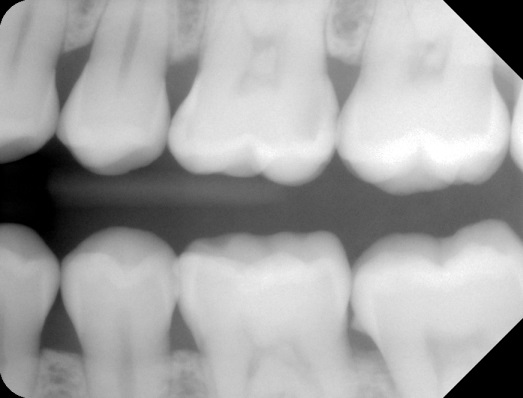

• Ακτινογραφικά απεικονίζονται σαν στρογγυλές ή ωοειδείς ακτινοσκιάσεις εντός του πολφικού θαλάμου ή των ριζικών σωλήνων.

Ασθενής 22 ετών με εντοπισμένους πολφόλιθους στους άνω γομφίους